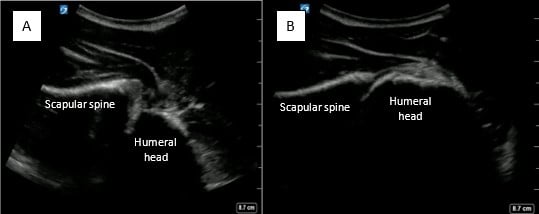

A 16-year-old male with history of recurrent shoulder dislocation and arthroscopic labral repair, presented with acute right shoulder pain after colliding with another player during basketball. The physical exam was notable for obvious right shoulder deformity, with an intact neurovascular exam. POCUS revealed an anterior shoulder dislocation without humeral fracture. After discussion with the family, the decision was made to proceed with an interscalene nerve block. The block was performed, and the shoulder was subsequently reduced successfully, confirmed by post-reduction POCUS (Figure 1). The patient was noted to have an asymptomatic ipsilateral diaphragm paralysis following the nerve block, which resolved within an hour, and he was discharged without complication. He did not require any opioids or procedural sedation throughout his ED stay, and tolerated both procedures well.

May2025-Pedi Interscalene_Fig 1.jpgFigure 1. A) Pre-reduction anterior shoulder dislocation B) Post-reduction